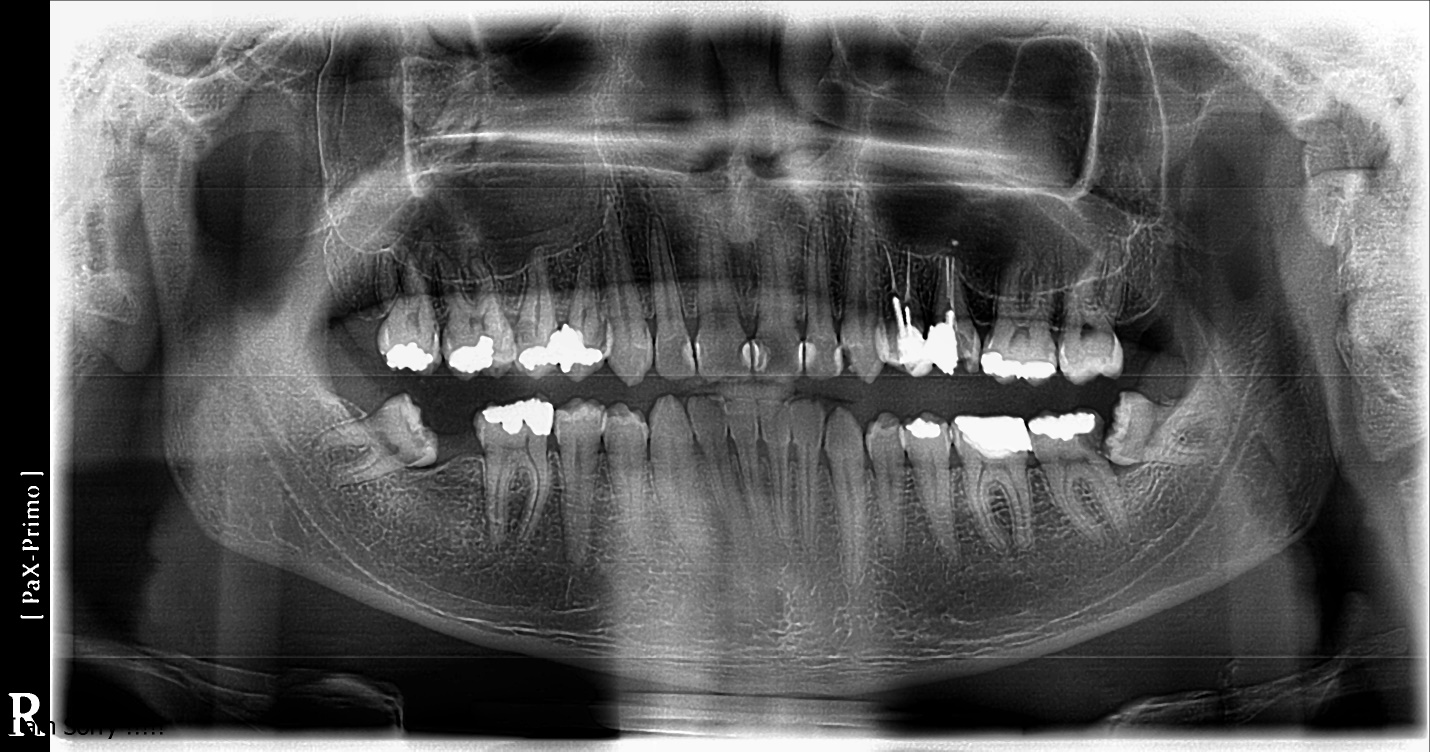

Figure 7. This panoramic radiographic shows no risk of nerve injury.